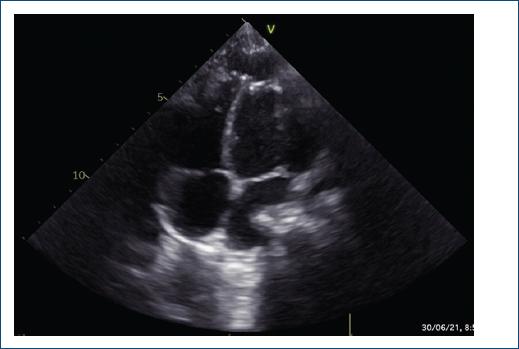

Se realizó ecocardiografía de control, en la cual se evidenció el aneurisma excluido (Fig. 3). Sin embargo, al año de seguimiento, mediante ecocardiografía se evidenció un defecto residual en el parche, con dos fugas residuales de 1.5 y 2.5 mm, con cortocircuito bidireccional en la punta del ventrículo izquierdo hacia la bolsa residual pericárdica, con función ventricular sistólica conservada, discinesia e hipocinesia de la punta ventricular izquierda (en el sitio del parche quirúrgico) (Fig. 4).

Figura 3 Ecocardiografía que muestra el aneurisma ventricular izquierdo excluido, con el parche de pericardio en posición, sin fugas residuales.